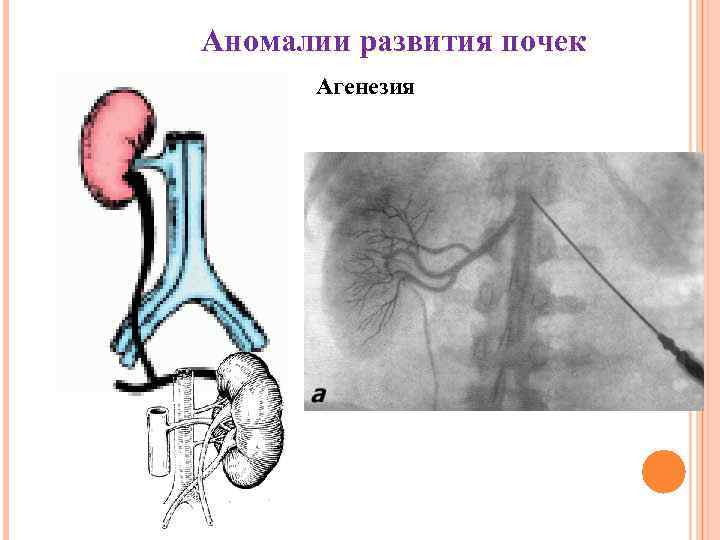

Аномалии развития почек Агенезия

Аномалии развития почек Агенезия